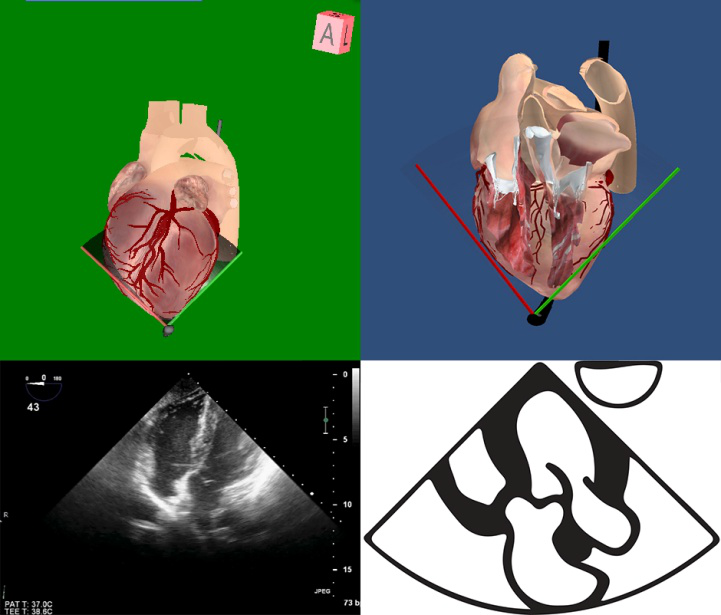

TEE切面可用来评估二尖瓣系统的每一部分,检查时将探头送至食管中段,操纵探头调整成像的角度使声平面对准二尖瓣环中心,探头晶片置于0~10度食管中段4腔心切面后开始旋转声平面,依次获得食管中段二尖瓣交界切面、食管中段左心室2腔切面、食管中段左心室长轴切面,在各个标准切面上可以观察不同小叶的功能状态,各个小叶与标准切面的对应关系如下图所示。

图10 TEE评价二尖瓣形态和功能的基本切面(标注二尖瓣分区)

TEE切面与二尖瓣分区的对应关系可用于二尖瓣脱垂部位的判断,但要注意的是:一定要将2D或3D图像与二尖瓣模型对应起来,不理解切面和模型之间的空间关系,直接用文献上的分区对应实际的超声图像会导致定位不准和交流障碍(图11,12,13,14);另外,经胃底基底段短轴切面对诊断瓣叶裂和穿孔很有帮助,彩色多普勒可以提供有关反流束起源的信息(图14)。

图11四腔心切面显示二尖瓣后叶P2区脱垂

图12 5腔心切面显示二尖瓣前叶A1区脱垂

图13食管中段左室长轴切面显示二尖瓣后叶P2区腱索断裂并脱垂

图14经胃底基底段短轴切面。示二尖瓣前后叶,P3区位于“扇形”的顶点